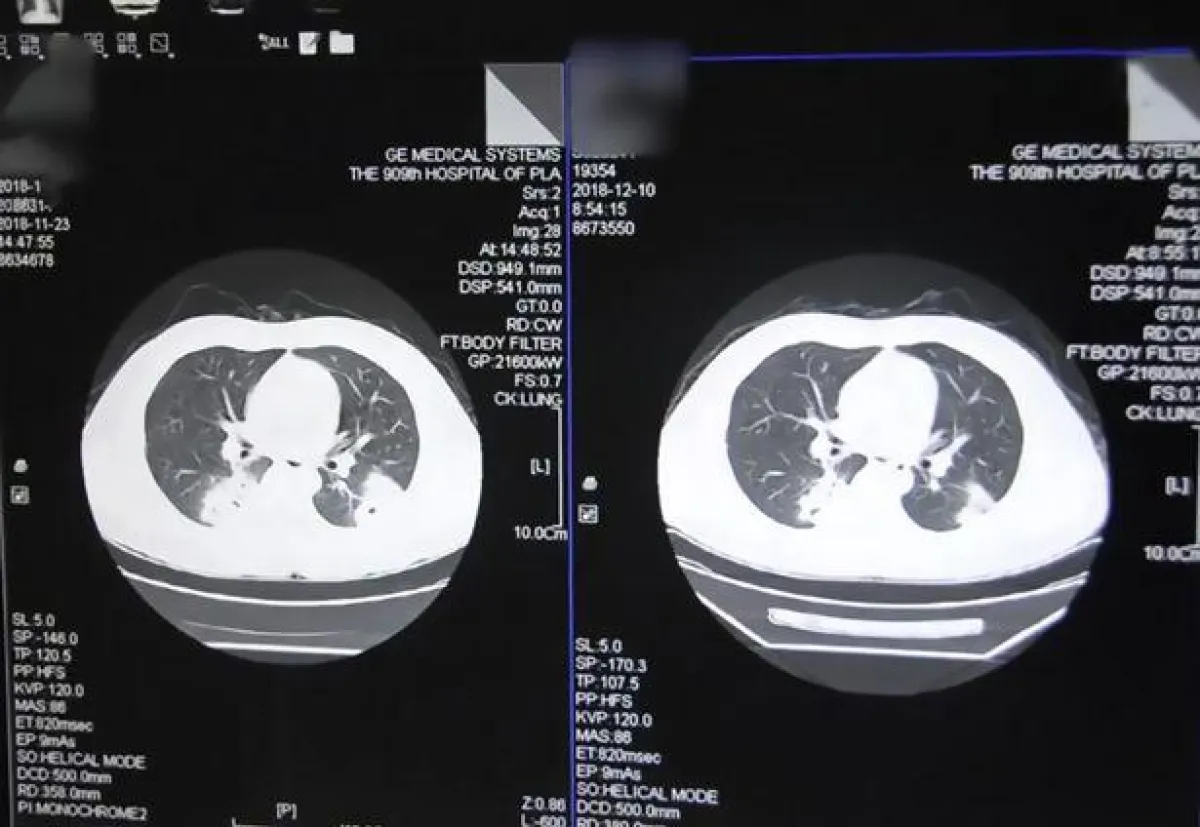

وقد أُدخل الرجل إلى المستشفى بالطوارئ، حيث أكدت الأشعة السينية أنه يعاني من التهاب شديد في الرئة، وأكدت التقارير الطبية أن سبب ذلك هو استنشاقه المتكرر لجواربه الخاصة، وقد أُبقي هذا الرجل في المستشفى للعلاج.